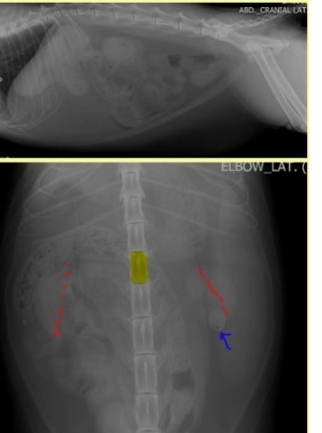

- 방사선 사진에서는 복강 내 독립된 원형 또는 타원형의 미네랄 음영(mineral opacity)을 갖는 연부 조직 병소처럼 보임. (PubMed)

- 윤곽이 비교적 규칙적이며, 내부 중심부가 덜 밀도(more lucent) 하거나 가장자리에 껍질(shell-like rim)을 가진 모습이 관찰되는 경우가 있음. (PubMed)